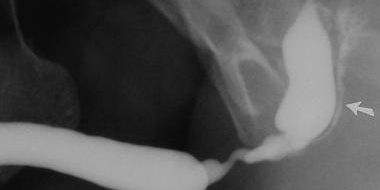

In the examination, the outer opening of the urinary canal must be examined and the penis must be inspected for signs of surgical history. Then, the uroflowmetry test, which is known as the urination test, must be performed. This test reveals a weak urine flow rate. The typical “curved stream” of urethral stricture patients is observed. An x-ray of the urethra called a retrograde urethrography is taken.

Retrograde urethrography must certainly be performed on a fluoroscopy table and blindly performed urethral radiography procedures with usual x-ray devices by administering contrast agents must not be preferred. It is better that the urethrography procedure is performed by the surgeon that will perform the surgery. Because the surgeon can adjust the rate of contrast agent injection as she is aware of the degree and location of the stricture in her patient. Therefore, the pain and urethrovascular reflux associated with the administration of the contrast agent with too much pressure will be prevented. Moreover, the surgeon who personally observes the fluoroscopic control will be able to decide whether or not the procedure has been sufficient, and whether or not a voiding cystourethrography is required, meaning whether or not an x-ray will be taken during urination. Therefore, the initial impressions regarding the format of the planned surgery will have formed at this stage, while the patient is still on the fluoroscopy table. During the retrograde urethroscopy procedure, the patient must be placed in a right lateral position on the fluoroscopy table, extend the lower leg straight and bend the upper leg at the knee, moving it to the side as much as possible.